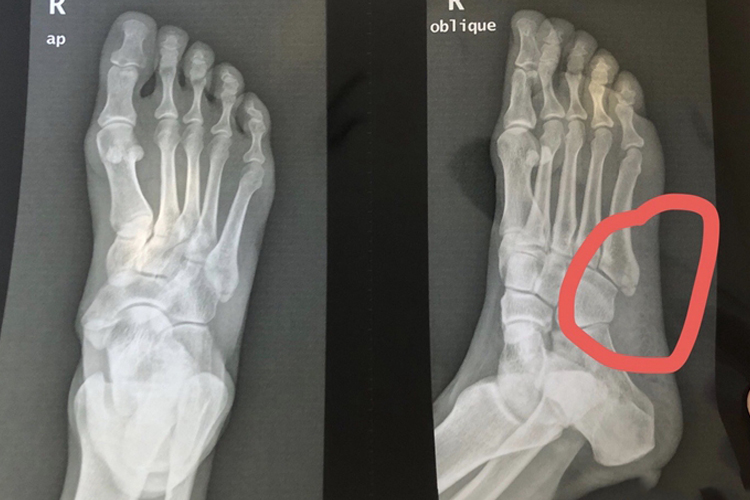

跖骨位于脚掌的中间部位,共五块,其中近端称为跖骨基底部,中间称体部,远端称跖骨头。基底部骨折后,可造成疼痛、肿胀等症状。

跖骨属于足骨,位于脚掌的中间部位,从内侧向外侧依次分为第1-5跖骨,其中近端称为跖骨基底部,中间称体部,远端称跖骨头。其中第5跖骨基底由于是松质骨,常因腓骨短肌猛烈收缩而易发生跖骨基底部骨折,骨折后可出现局部明显肿胀、发红,尤其以足外侧明显,同时伴随明显疼痛、活动受限现象。